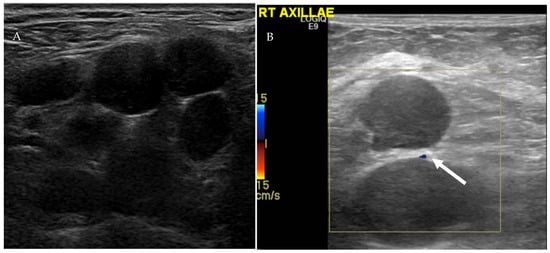

4.1.1. Ultrasound Evaluation of the Lymphatic System

- Prativadi, R.; Dahiya, N.; Kamaya, A.; Bhatt, S. Chapter 5 Ultrasound Characteristics of Benign vs Malignant Cervical Lymph Nodes. Semin. Ultrasound CT MRI 2017, 38, 506–515. [Google Scholar] [CrossRef]

- Dudea, S.M.; Lenghel, M.; Botar-Jid, C.; Vasilescu, D.; Duma, M. Ultrasonography of superficial lymph nodes: Benign vs. malignant. Med. Ultrason. 2012, 14, 294–306. [Google Scholar]

- Vassallo, P.; Wernecke, K.; Roos, N.; E Peters, P. Differentiation of benign from malignant superficial lymphadenopathy: The role of high-resolution US. Radiology 1992, 183, 215–220. [Google Scholar] [CrossRef]

- Ahuja, A.; Ying, M. Sonographic evaluation of cervical lymphadenopathy: Is power Doppler sonography routinely indicated? Ultrasound Med. Biol. 2003, 29, 353–359. [Google Scholar] [CrossRef]

- Ahuja, A.T. Ultrasound of malignant cervical lymph nodes. Cancer Imaging 2008, 8, 48–56. [Google Scholar] [CrossRef]

| US Criteria | Benign Lymph Node | Malignant Lymph Node |

|---|---|---|

| Size | <1 cm in short axis | ≥1 cm in short axis |

| Shape | Oval or elliptical | Round |

| Border | Indistinct | Sharp |

| Echogenicity | Hypoechoic | Very hypoechoic |

| Hilum | Maintained fatty hilum | Absent fatty hilum |

| Vascularity | Avascular or hilar vascularity | Peripheral or mixed |

| Resistive index | Low | High |